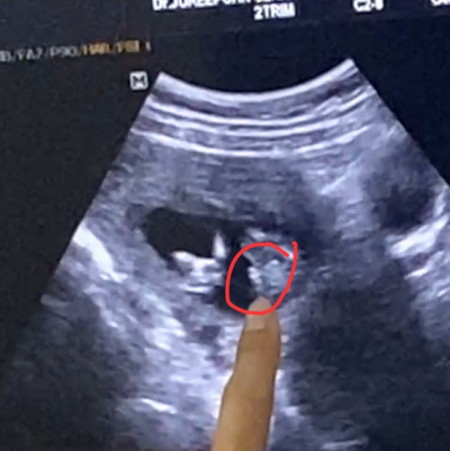

ผู้หญิง/ผู้ชาย คะแม่ๆ ช่วยดูหน่อยค่ะ

แม่ๆช่วยดูหน่อยค่ะ ว่าผู้หญิง/ผู้ชาย คุณหมอยังไม่แน่ใจค่ะ 😂😊

ช.มั้ยค่ะ

คุณแม่ of 1 แสนซน คุณชาย